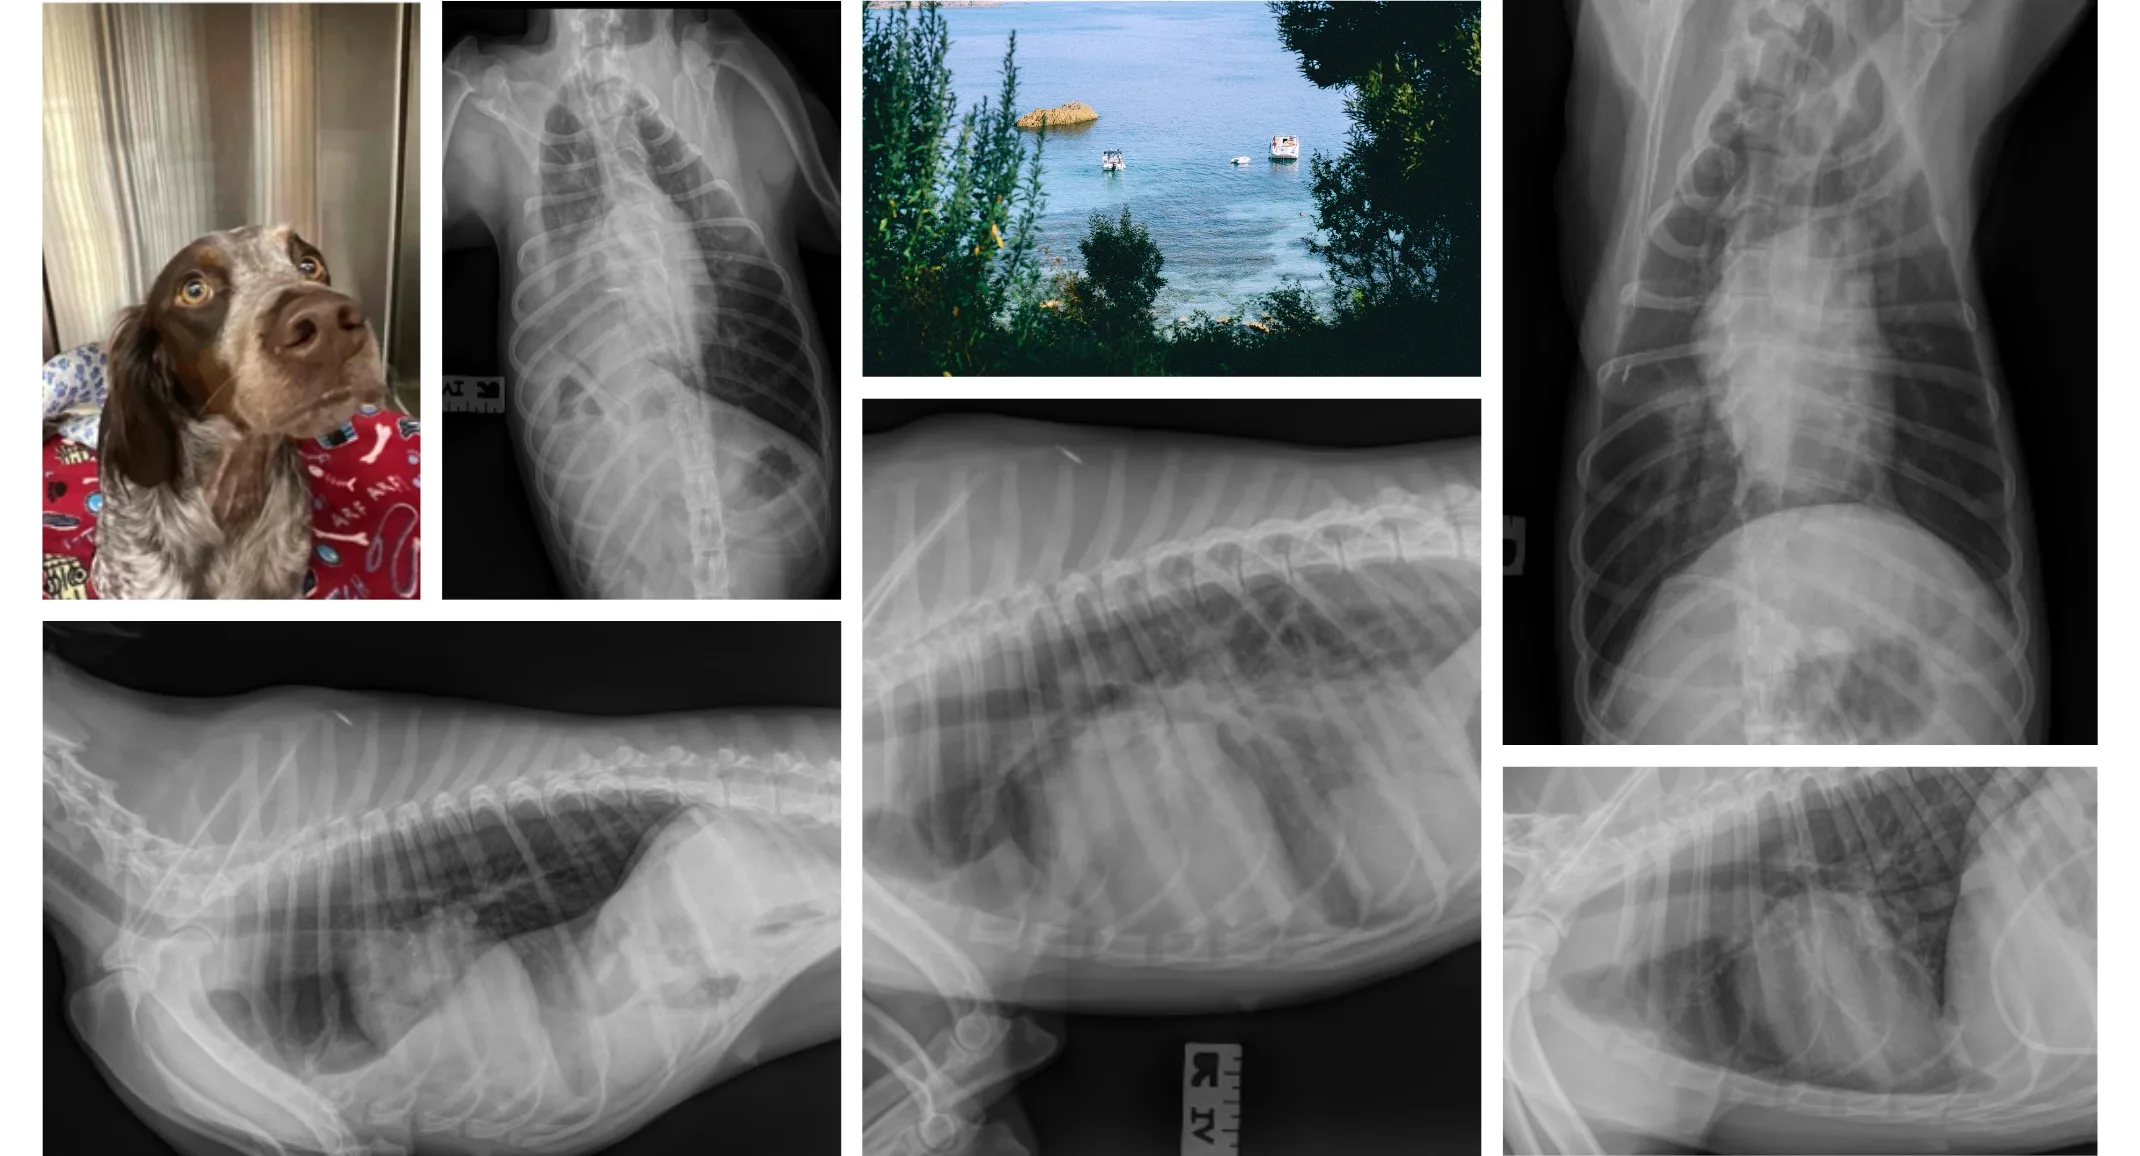

Marilyn is a 1.6-year-old Female Brittney Spaniel. She presented to an emergency veterinary clinic after being hit by a car. She had superficial wounds on her rear limbs. She was observed overnight without complications. The next day she was sedated for treatment of her wounds. During sedation, she developed anesthetic complications. She recovered from sedation with supportive care. Radiographs were performed.

A diaphragmatic hernia was revealed. The patient was referred to VSB emergency service for diagnostics and treatment. On admission to the emergency service, Marilyn was bright, alert, and responsive. She did not exhibit overt symptoms but did have decreased lung sounds on auscultation of the right hemithorax. A full assessment revealed that she had an ALT >1300 U/L and was suffering from preventricular contractions. She had obviously sustained severe trauma to the abdomen and thorax. She was treated for 24 hours with supportive care and the VPC’s resolved.

Marilyn returned for surgery 4 days later. She remained clinically asymptomatic. Her arrhythmia remained resolved and her ALT decreased to 257 U/L. Marilyn was prepped and clipped before induction to facilitate quick surgical intervention. Upon induction, Marilyn quickly developed hypotension and hypoxia. An expedited celiotomy revealed a large right-sided diaphragmatic hernia. The hernia contained the liver, gallbladder, duodenum, and part of the jejunum. The right lung fields were completely compressed by the herniated organs when placed in dorsal recumbency. The abdominal viscera were reduced to the proper location. Her condition stabilized. A large radial tear of the diaphragm was found that extended from the dorsal body wall to the sternum.

The viscera were retracted allowing reconstruction of the diaphragm. The diaphragmatic tear originated in the right crus and transversed adjacent to the esophageal hiatus and caval foramen before terminating in the pars sternalis. Respiration was controlled with a ventilator while the diaphragm was carefully sutured. Because the diaphragm avulsed from the esophagus and cava tedious suturing was necessary. A thoracostomy tube was placed for controlled reinflation of the lungs. No complications occurred during the surgery. Marilyn recovered with supplemental oxygen. Controlled evacuation of the pneumothorax helped prevent re-inflation injury. Vital parameters remained stable. The thoracostomy tube was removed the following day. Radiographs confirmed normal thorax.